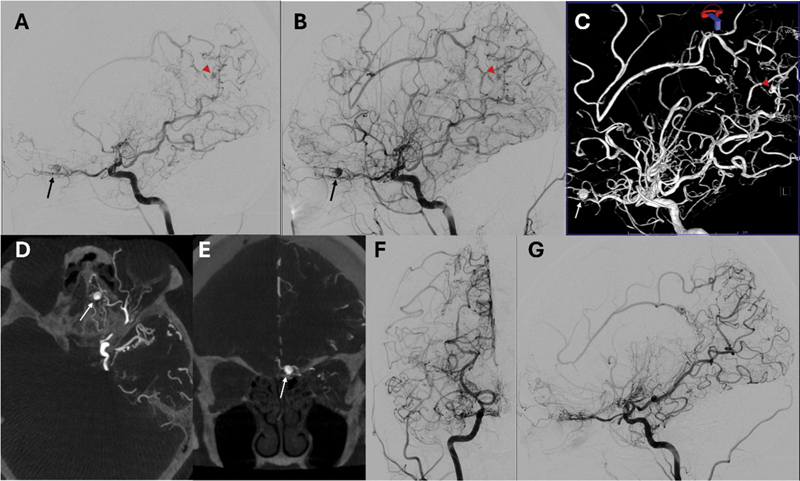

Spontaneous acute subdural hematoma is uncommon and usually caused by coagulopathy or other bleeding disorders, malignancy, intracranial hypotension, and abnormal intracranial vessels. We present unique cases of acute spontaneous subdural hematoma from moyamoya disease. There are a few cases reported, and we review previous literature and describe bleeding sources from aneurysms related to moyamoya disease in highly unusual locations.